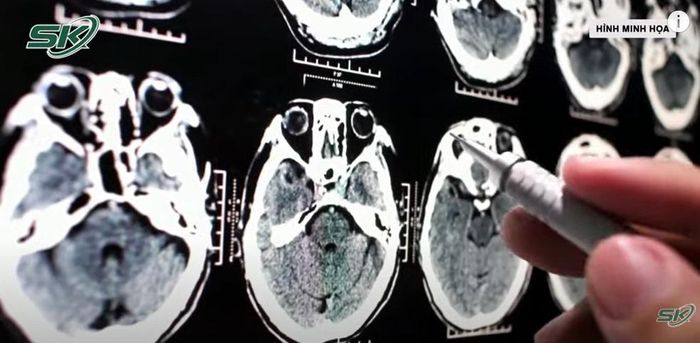

U màng não là sự xuất hiện của khối u trên màng não, đây là phần màng bao phủ não bộ và tủy sống bên trong hộp sọ. Khối u màng não thường phát triển khá chậm, có tỷ lệ lành tính cao.

Kết quả chụp MRI sọ não cho thấy bệnh nhân có khối u ngoài trục vùng trán trái, kích thước khoảng 4 cm, gây chèn ép và phù nhu mô não nghiêm trọng, đẩy lệch đường giữa não hơn 6 mm.

Đa số bệnh nhân bị u màng não sẽ đối mặt với những cơn đau nhức đầu.